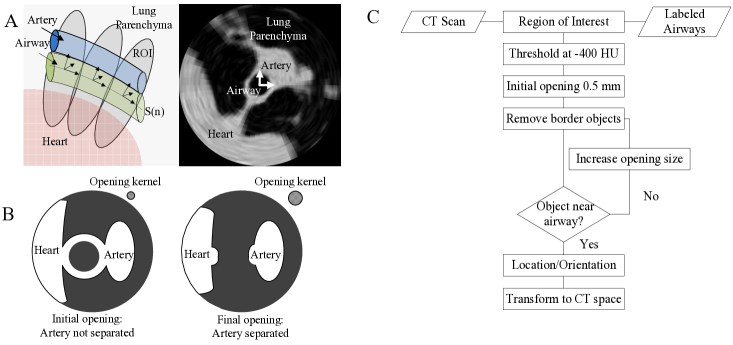

Three preliminary steps were performed to reduce noise and decrease the signal from unwanted structures. A 3×3333\times 3 median filter was first applied to reduce the non-Gaussian noise inherent in low-dose scans. The scans were then thresholded at -400 HU to separate the soft tissue (0 HU) from the lung parenchyma (-900 HU) within the lungs. Structures such as bone (200 HU) and fat (50 HU) were not eliminated after thresholding. However, because these structures do not appear in the lungs, they are highly unlikely to affect the results of the segmentation.

We used the results of our previously reported airway segmentation [15] to remove the airway walls, a potential source of error in vessel segmentation. The airway was enlarged by dilation with a 2 mm isotropic kernel. The dilated airway was then subtracted from the CT image to remove the airway walls. Figure 1 illustrates the application of this operation to a 3rd generation airway/artery segment.

Refer to captionRefer to captionmissing-subexpression\begin{array}[]{cc}\includegraphics[width=310.76122pt]{MEDIANPAPER.pdf}\end{array}

Figure 1: Removal of the airway walls by dilation of the airway segmentation and subtraction from the thresholded CT image.